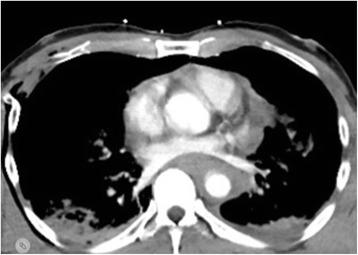

An incomplete traumatic rupture of the ascending aorta is a rare but life-threatening condition. Hence, the assessment of the extent of the injury prior to therapy is crucial. We report a case of a 50-year-old male with traumatic aortic rupture who underwent emergency surgery after the evaluation of computed tomography scan (CT-scan). The surgical treatment involved replacement of the ascending aorta and stent implantation in descending aorta due to its covered rupture.

升主动脉不完全性创伤性破裂是一种罕见但危及生命的病症。因此,在治疗前评估损伤程度至关重要。我们报告一例50岁男性创伤性主动脉破裂患者,在计算机断层扫描(CT扫描)评估后接受了急诊手术。手术治疗包括升主动脉置换以及因降主动脉覆膜破裂而行的支架植入术。